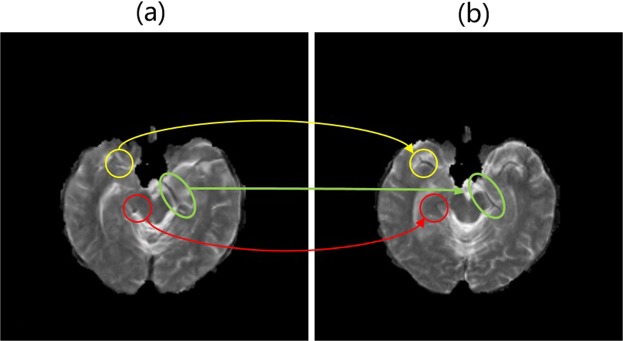

Although our approach generally achieves excellent performance, we recognize that in some cases our generated images are still not as good as real images at tiny structures. As illustrated in Fig. 11, there are also abortive cases where tiny structures may be mistaken. In the yellow circle, the eyebrow-like structure is missing. The red circle indicates a non-existent round structure which might be confounded with the vessel. In the green circle, the learned structure seems to be discontinuous which might give rise to perplexity for radiologists to make a diagnosis. In the future, we will improve our algorithm to describe more tiny structures.

Figure 11.

An abortive sample in our generation results: (a) . (b) T2. Circles in indicate some misdescription of tiny structures. Circles in different colors indicate different problems.